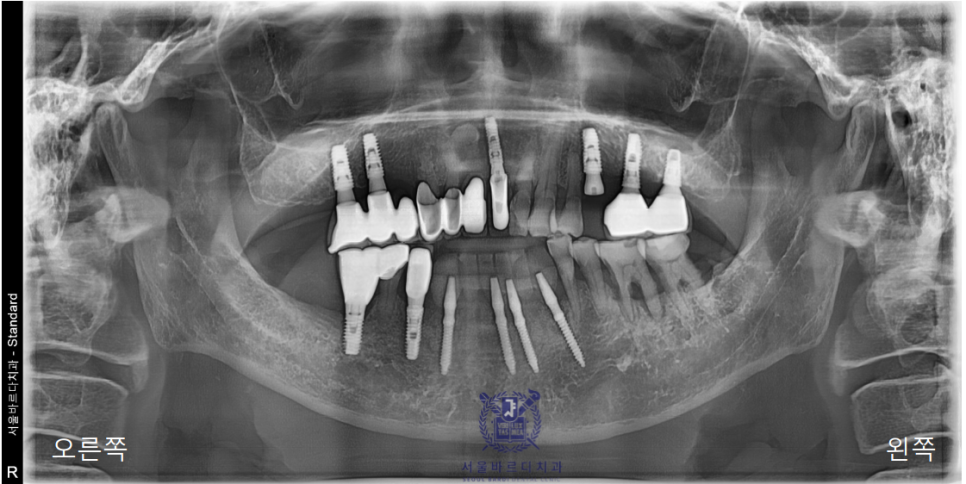

일단 파노라마 사진을 찍어 전체적인 상태를 체크해드렸습니다.

이미 다수의 보철과 임플란트를 하셨고,

앞니쪽은 조금 더 자세하게 보기위해 치근단 엑스레이를 추가로 촬영하였습니다.

양쪽 송곳니 두개를 이용해 앞니 6개의 보철을 사용하고계셨는데

지지해주던 양쪽 송곳니쪽에 문제가 생겨서

염증이 이미 많이 진행된 상태였습니다.

문제가 생긴 아래 앞니 부분은 이미 신경치료도 다 되어있는 상태였는데도

다시 뿌리 끝까지 염증이 생겨 결국 치아까지 많이 흔들리고,

환자분의 통증과 불편감이 상당했기에 충분한 상담을 통해

발치 후 임플란트를 하는 것으로 방향을 잡아드렸습니다.

전체적으로 치주염도 심한 상태였고

왼쪽 위 역시 앞니처럼 한참 고생하시다가

왼쪽 위 역시 가장 이상적인 위치에 성공적으로 임플란트를 식립하였습니다.

아래 앞니는 6개의 치아를 안정적으로 유지할 수 있는

견고한 4개의 뿌리를 식립하였고

왼쪽 위는 큰어금니 다음으로 중요한 역할을 수행할 작은

어금니에 맞는 사이즈로 식립하였습니다.